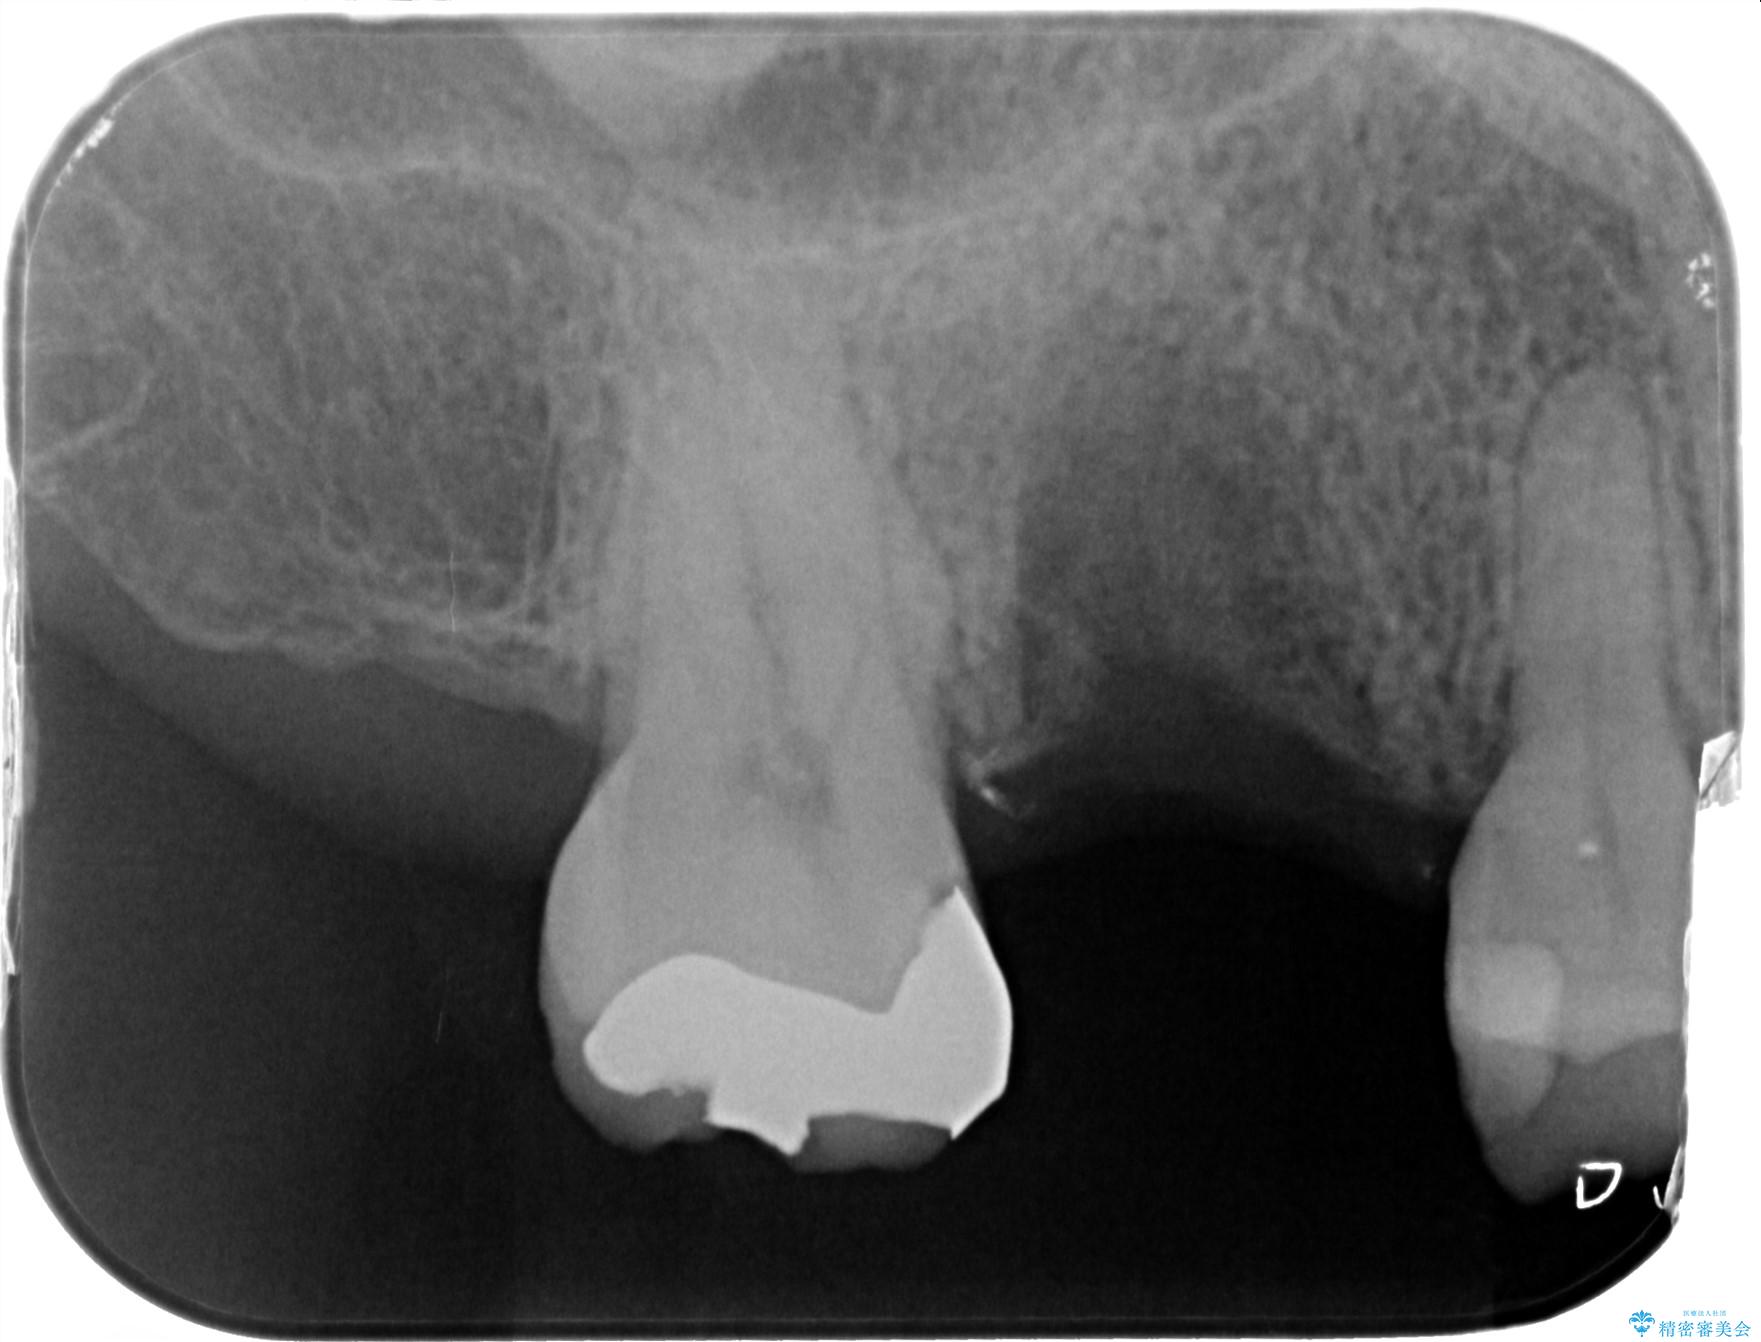

インプラント治療を行ったことで前後の歯を削らずに咬合機能の回復をすることができ、大変ご満足いただけました。